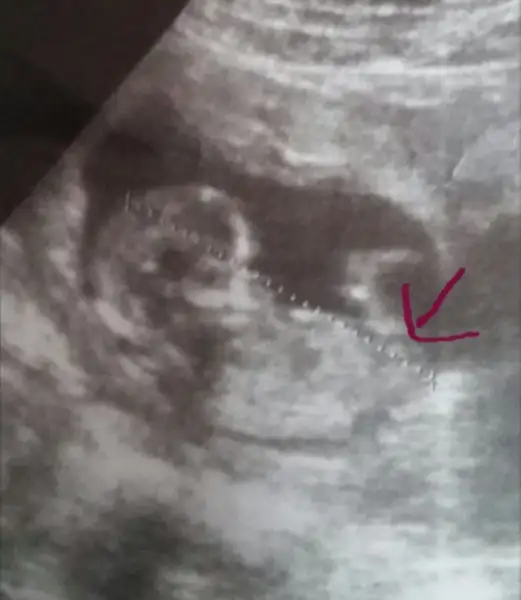

BeyazOrkidem canım senin icin yakından çektim bide gösterdiğim yerde bi cıkınti var. Doktorumda gösterdi ama emin konuşamadi. Sence o pipi olabilirmi. Sen anliyosun diye soruyorum canim valla sana zahmet bakarmısın